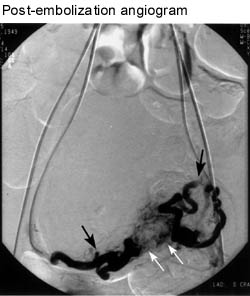

Notice how much less blood flow is present after the embolization. The black arrows are pointing to the blocked ends of the uterine arteries. The fibroids no longer get any blood.